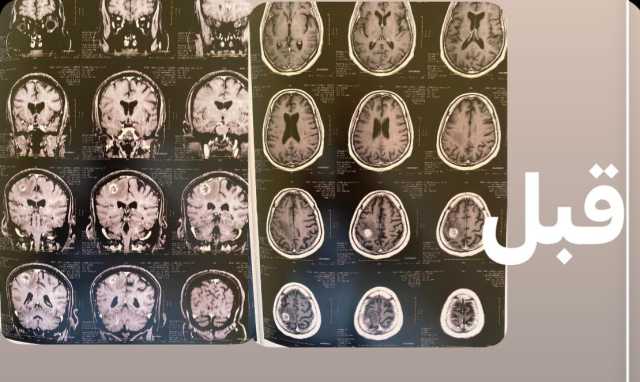

كانت المريضة قد حضرت إلى المستشفى وهي تعاني من تشنجات متكررة وتدهور في درجة الوعي وشلل تام بالجانب الأيسر من الجسم، وبعد إجراء الأشعات والفحوصات اللازمة، تبين وجود ورم بالفص الأيمن للمخ يضغط على منطقة الحركة، مما تسبب في تلك الأعراض.

وأوضح  الدكتور السيد فاروق، وكيل الطب العلاجي، أن الفريق الطبي بالمستشفى نجح بفضل الله في استئصال الورم بالكامل من خلال جراحة دقيقة أجريت داخل المستشفى، مشيرًا إلى أن العملية تمت بنجاح كامل، وتحسنت حالة المريضة بعد الجراحة واستعادت وعيها الطبيعي وتوقفت التشنجات، وهي الآن تحت العلاج الدوائي والعلاج الطبيعي لحين تمام الشفاء.